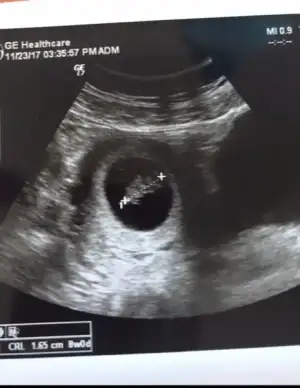

Bn 3kez gittim ilkinde sadece kan verdim 2.de kese 3.de kalp sesini duyduk çok şükür